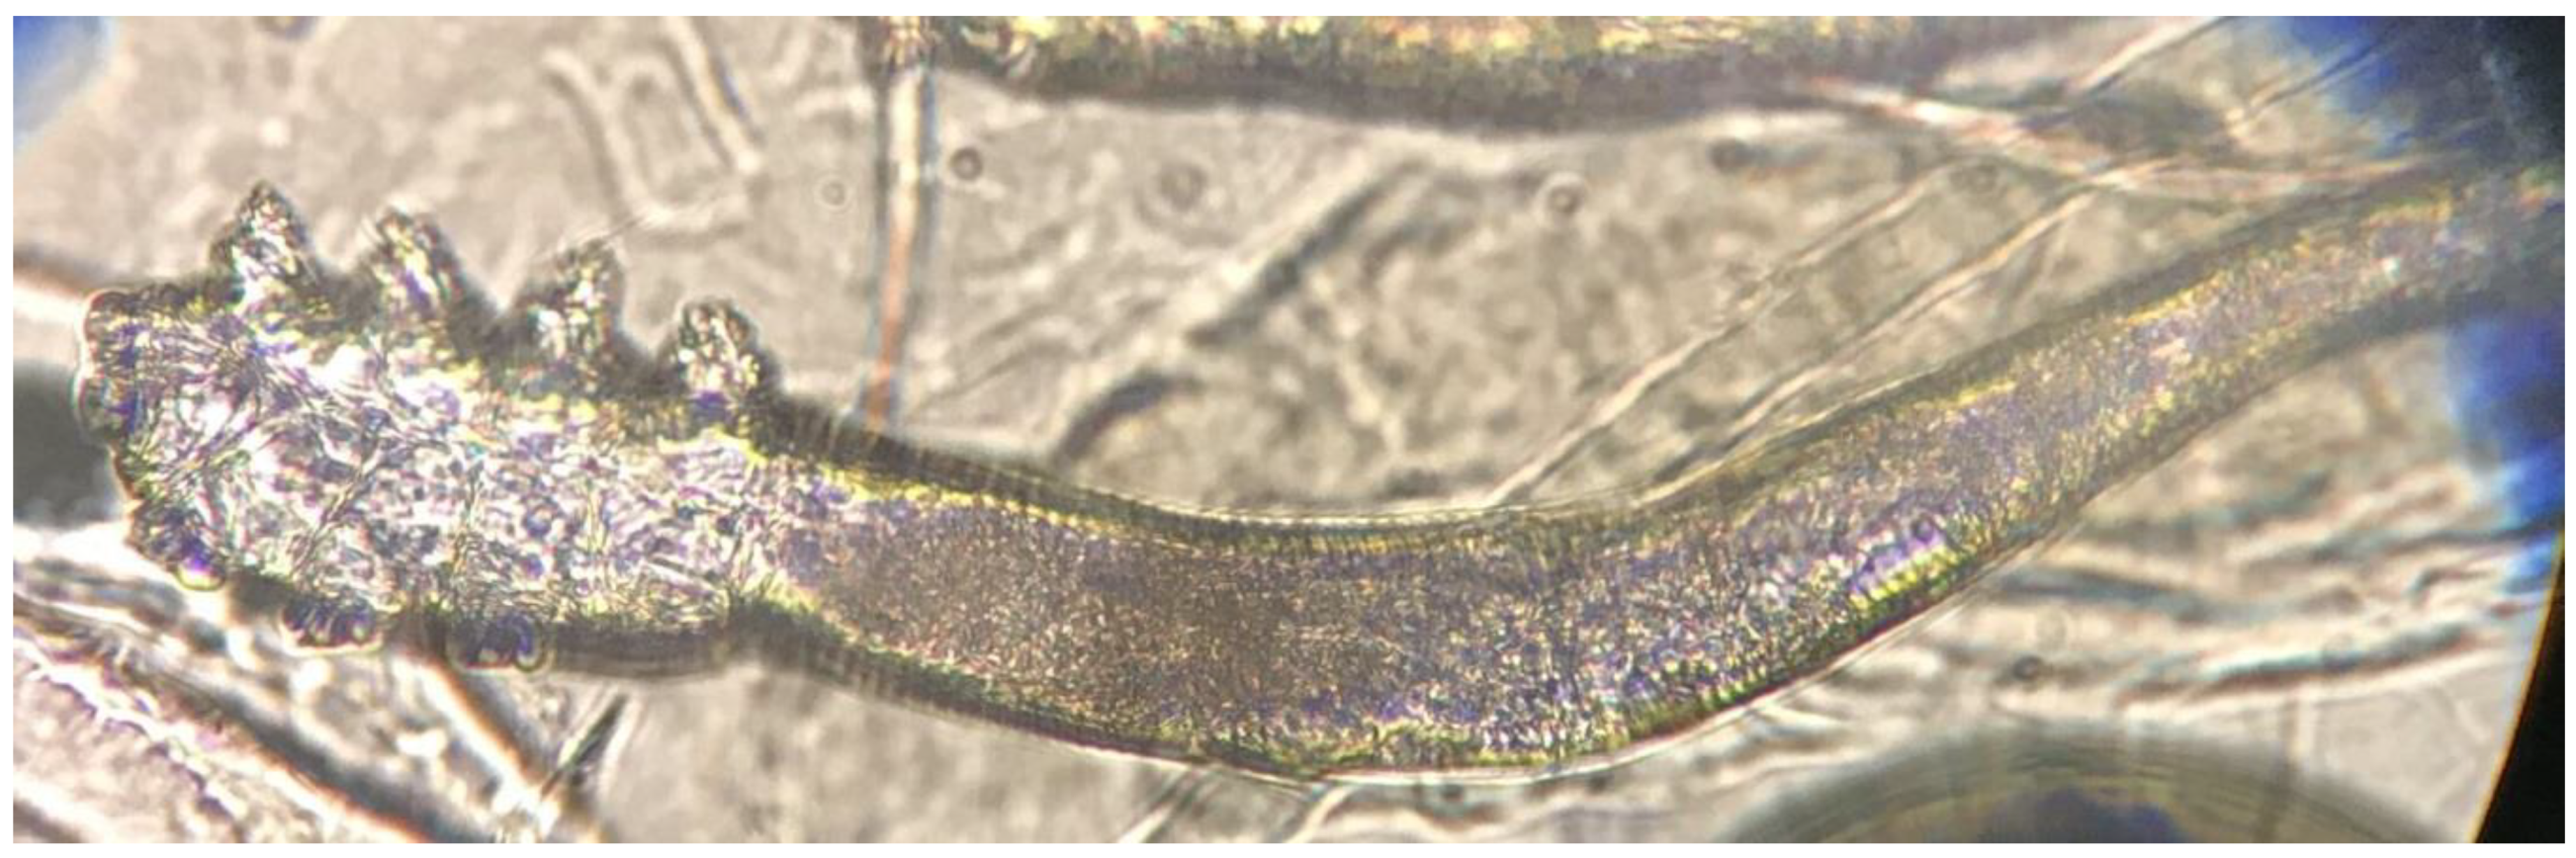

2.2. Demodex Investigation